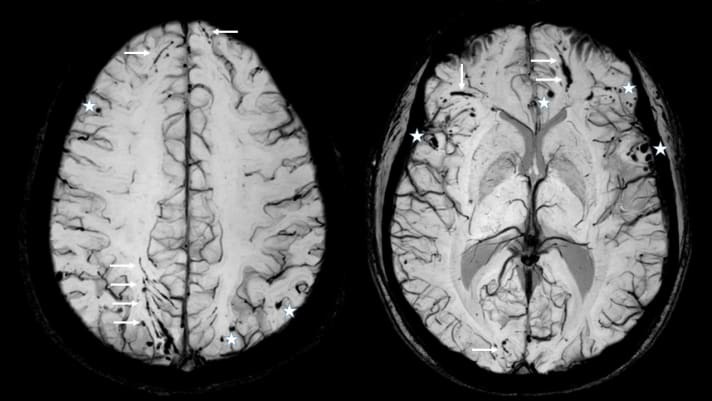

MRT eines Schädel-Hirn-Traumas mit der Suzeptibilitäts-gewichteten Technik (SWI): Neben den punktförmigen Einblutungen im Hirngewebe (weiße Sterne) findet man weitere Rissverletzungen (sogenannte Scherverletzungen, weiße Pfeile), die man u. U. nur in dieser Technik und auch noch Jahre nach einem Unfall finden kann. Entsprechend wo sie auftreten, entstehen entsprechende Beschwerden. Aufgrund des berichteten Unfallhergangs war das Schädel-Hirn-Trauma nur als “leicht” eingestuft worden - bei diesem Patient war daher kein MRT oder CT gemacht worden.Foto: Prof. S. UlmerMRT eines Schädel-Hirn-Traumas mit der Suzeptibilitäts-gewichteten Technik (SWI): Neben den punktförmigen Einblutungen im Hirngewebe (weiße Sterne) findet man weitere Rissverletzungen (sogenannte Scherverletzungen, weiße Pfeile), die man u. U. nur in dieser Technik und auch noch Jahre nach einem Unfall finden kann. Entsprechend wo sie auftreten, entstehen entsprechende Beschwerden. Aufgrund des berichteten Unfallhergangs war das Schädel-Hirn-Trauma nur als “leicht” eingestuft worden - bei diesem Patient war daher kein MRT oder CT gemacht worden.